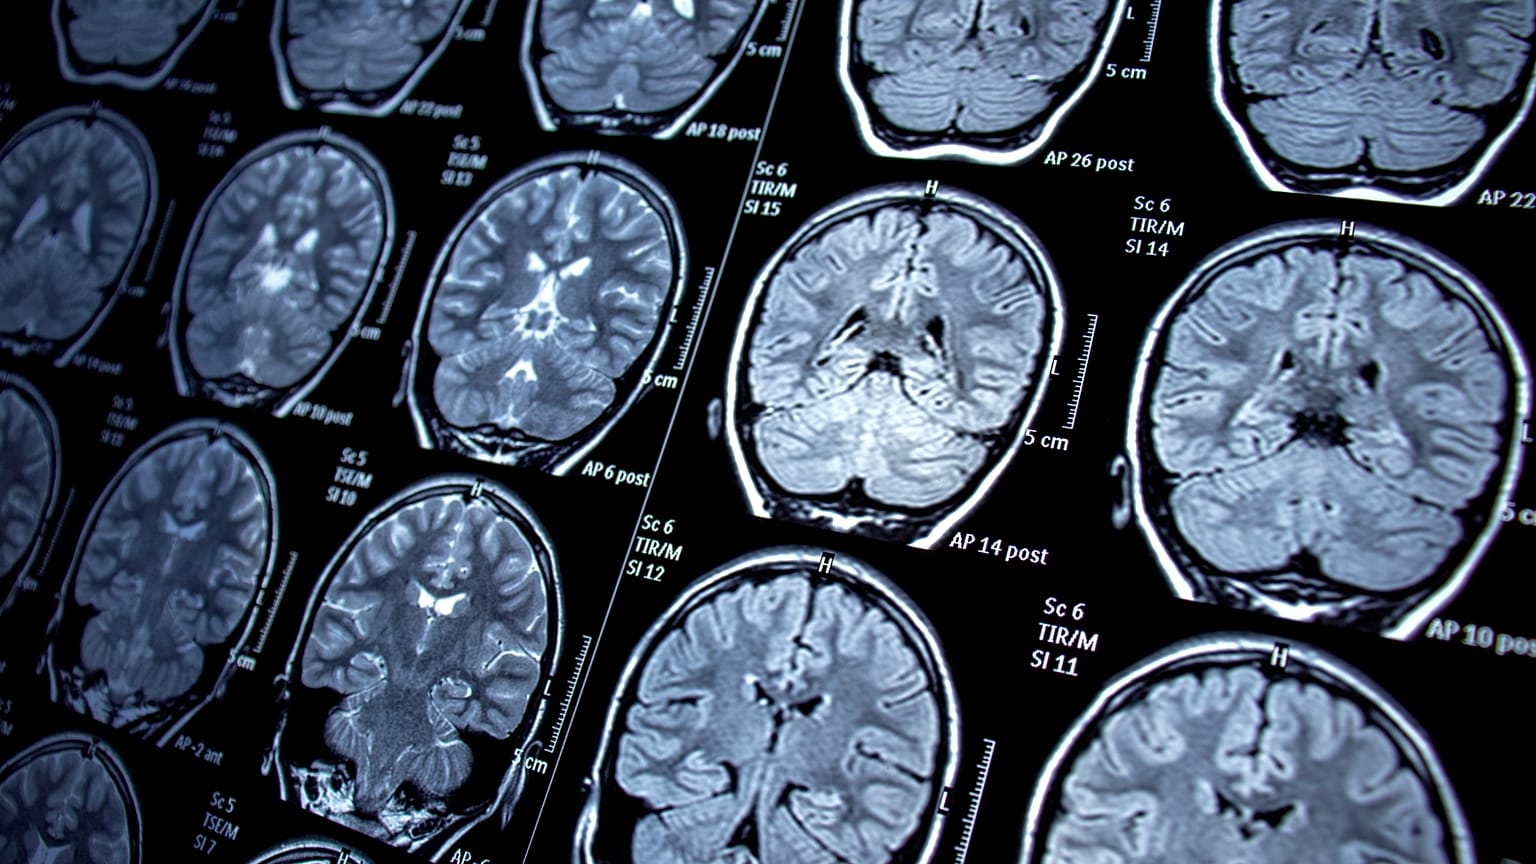

La resonancia magnética utiliza campos magnéticos para producir imágenes detalladas de órganos, huesos y otras estructuras del interior del cuerpo.

La resonancia magnética utiliza campos magnéticos para producir imágenes detalladas de órganos, huesos y otras estructuras del interior del cuerpo. Derechos de autor  Canva

A diferencia de la mayoría de las exploraciones, la resonancia magnética utiliza campos magnéticos para producir imágenes detalladas de las estructuras internas del cuerpo, en lugar de radiación

IRM son las siglas de resonancia magnética. Es un tipo de exploración médica que utiliza campos magnéticos para producir imágenes detalladas de órganos, huesos y otras estructuras del interior del cuerpo. A diferencia de muchos otros tipos de exploraciones, las resonancias magnéticas no utilizan radiación.

Los médicos solicitan una resonancia magnética para diagnosticar cáncer, lesiones cerebrales, vasos sanguíneos dañados y otras afecciones. Las exploraciones de cuerpo entero pueden durar una hora o más, y los pacientes permanecen inmóviles dentro de un tubo cilíndrico.